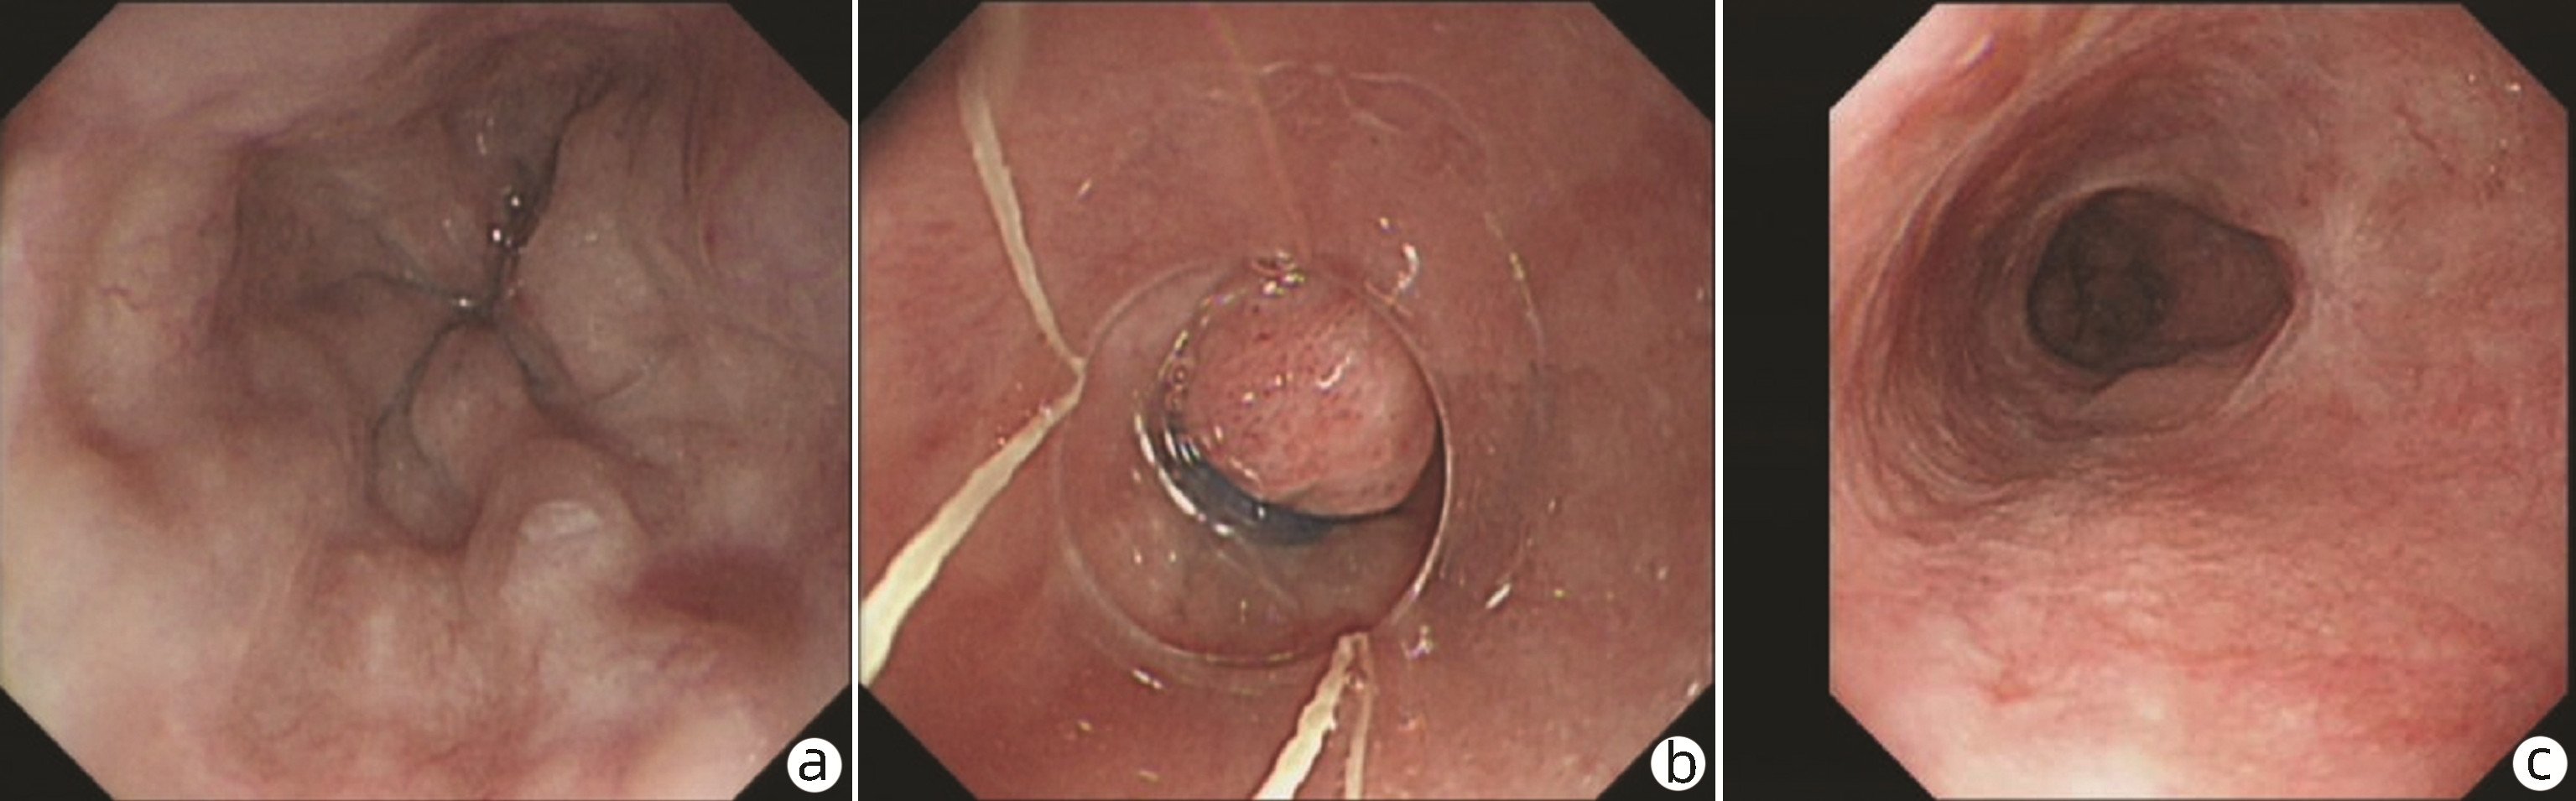

内镜下序贯套扎治疗食管胃伴十二指肠静脉曲张1例报告

文皓, 何朝晖, 蒋彤, 石国庆

2023, 39(3): 637-639. DOI: 10.3969/j.issn.1001-5256.2023.03.024

摘要(891) HTML (275) PDF (2676KB)(111)

摘要: